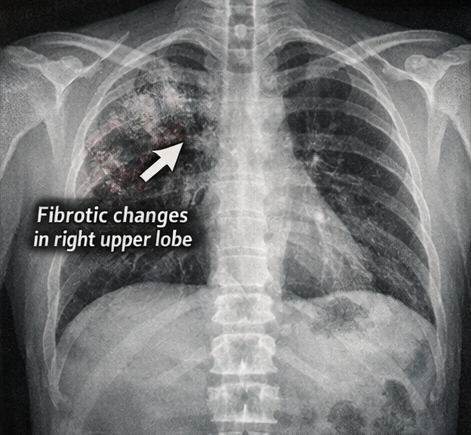

A 62-year-old male presented to the emergency department with low-grade fever, progressive headache, and intermittent vomiting for 3 weeks, followed by altered sensorium and unsteady gait for 2 days. He reported generalized weakness and reduced appetite but denied seizures or recent head trauma. There was no history of cough, hemoptysis, or known tuberculosis contact. The patient had poorly controlled type 2 diabetes mellitus for 10 years and had lost approximately 5 kg over the preceding 2 months. There was no history of HIV infection or chronic steroid use.

Tuberculous meningitis remains a devastating neurological emergency with high rates of mortality and neurological disability. The subacute presentation and low sensitivity of conventional microbiological tests often delay diagnosis. CSF typically shows lymphocytic pleocytosis, elevated protein, and low glucose; however, microbiological confirmation may require nucleic acid amplification tests or culture, which can take time. Neuroimaging commonly demonstrates basal meningeal enhancement, hydrocephalus, and infarcts due to vasculitis, all of which correlate with worse outcomes.